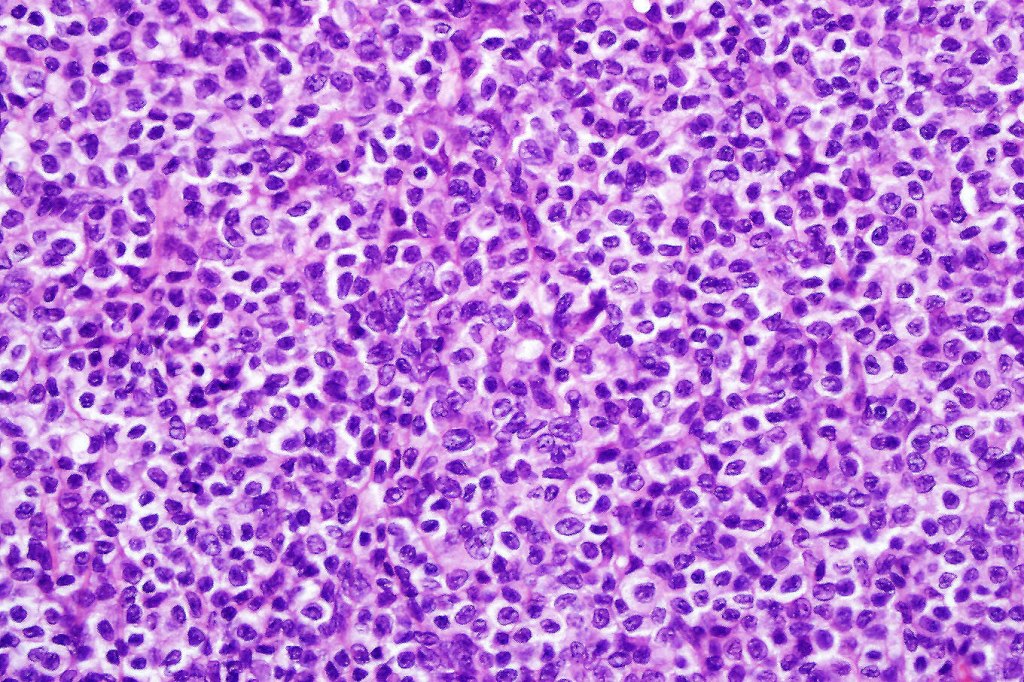

Histological features

The histological hallmark of mycosis fungoides is the presence of large atypical lymphocytes with a convoluted/cerebriform nuclear border (Sézary cells). These may be found at the epidermal-dermal jnuction and as collections within the epidermis (Pautrier microabscess). These are most easily found in plaque stage disease. The epidermal component can be subtle in patch stage disease and is often lost in tumor stage dsease. The classification into patch, plaque & tumor stage disease is less helpful histologically as the features merge from one to the other. It is all a matter of degree.

Tumor Stage Disease

•Epidermotropism is often minimal or absent

•Dense, broad diffuse or nodular, dermal infiltrate often extending into the subcutaneous fat

•Abundant Sézary cells. Frequently accompanied by very pleomorphic forms

•Mitoses often abundant, frequently abnormal

•CD30 expression correlates with transformation (cells X4 size of small lymphocytes comprising 25% or more of the infiltrate or the presence of a distinct large nodule)